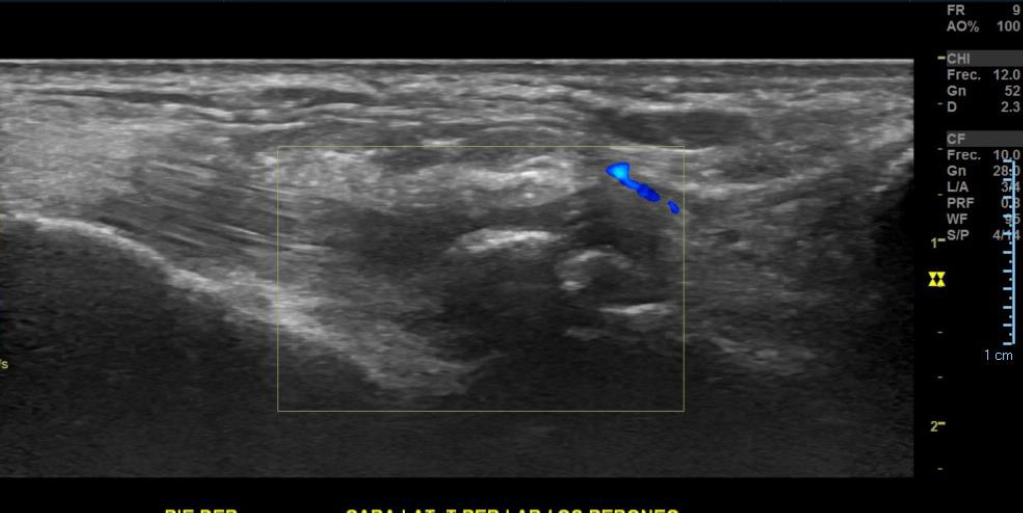

Imagen con aspecto de os peroneo de contornos corticales irregulares, con cambios inflamatorios de las partes blandas adyacentes, pudiendo estar en relación a fractura a este nivel.

Impresión diagnóstica: Imagen con aspecto de os peroneo de contornos corticales irregulares, con cambios inflamatorios de las partes blandas adyacentes, pudiendo estar en relación a fractura a este nivel. Se sugiere evaluar con radiografía.

Tendinosis del peroneo largo en su región distal.